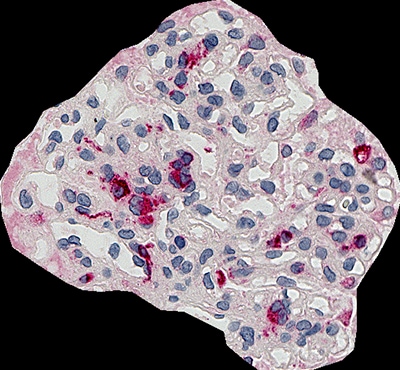

CD68(巨噬细胞)肾小球占用率分析例

下面是CD68(巨噬细胞)肾小球占用率分析的一个例子。HE染色后,捕捉肾脏活检的鸟瞰图。通常情况下,当样本较厚时,很难对图像进行聚焦,但Z-stack图像捕捉使显微镜能够聚焦整个图像。

肾小球占用率:4.3%